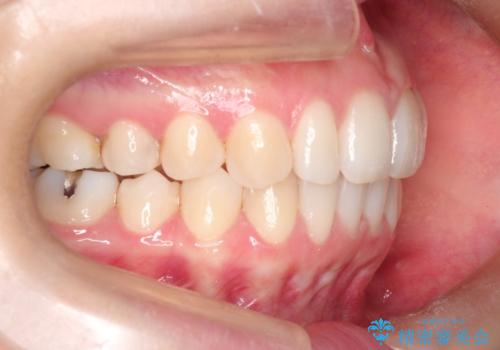

初診時の歯並びの状態としては、上下ともに前歯部の中等度のがたつきがあり、特に左上の前歯が1本内側に入り込んでしまっている状態でした。

また、2mm程度の正中離開がありました。

抜歯なし/インビザラインによるマウスピース矯正にて治療を行いました。

内側に入り込んでしまっている歯を出してくることに非常に時間がかかりましたが、一度歯を歯茎の方へ押し込みそして前へ出してくる2段階の治療を行いました。

見た目、嚙み合わせ及び、治療期間や施術内容に大変ご満足いただきました。